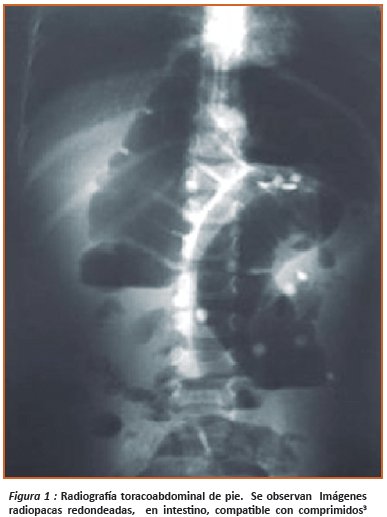

Es importante también solicitar una radiografía simple de abdomen, que confirma, el diagnóstico y la severidad del cuadro clínico, valora indirectamente la presencia de hierro en el tracto gastrointestinal como material radio-opaco, y permite valorar perforación intestinal si se presenta5,7 ( Figura 1).

Una Radiografía simple de abdomen: En el que Se aprecian imágenes radio opacas en la luz intestinal compatibles con intoxicación (Figura 2).